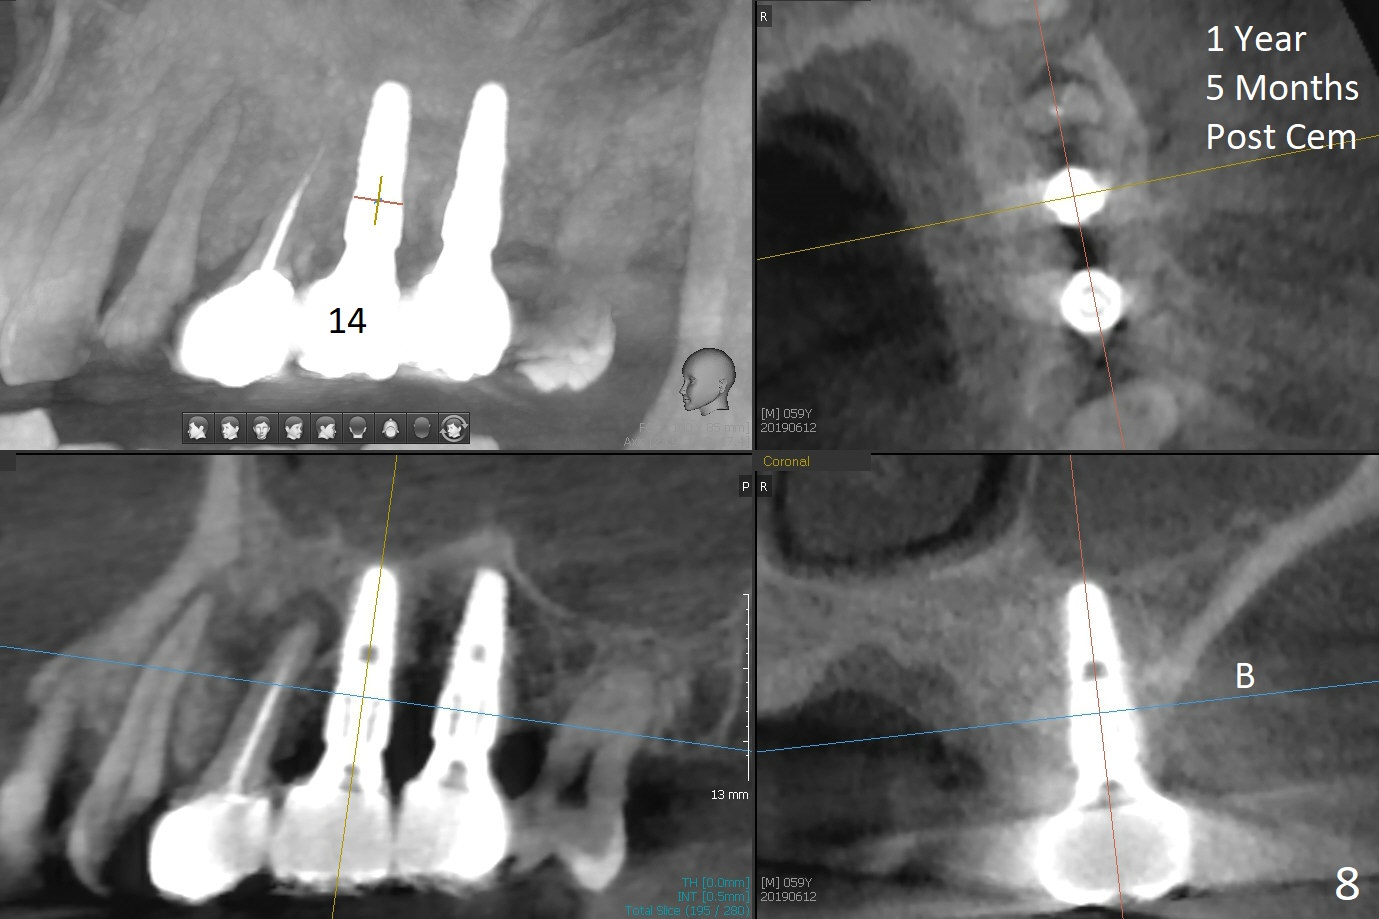

When 1.2 mm drill is used for osteotomy at #14 and 15, the bone feels to be soft (Fig.1). After change in trajectory (Fig.2), Expander 1 (Fig.3: E1, 1/1.6 mm) can be inserted at #14 and 15, while E2 (1.2/2.3 mm) cannot at full length at #14, suggesting hard bone. Osteotomy continues with drills until 4.1x14 mm, followed by insertion of E4 (2.4/3.7 mm) at #14, while osteotomy goes on until E3 (1.7/3.1 mm) at #15 (Fig.4). A 4.5x12 mm SM implant is placed with 50 Ncm (with insertion of a 5.8x4(2) mm abutment as a guide for #15 osteotomy, Fig.5). The apical portion of the osteotomy at #15 (Fig.5 red line) is finished with drills, leading to placement of a 4.5x12 mm implant (>50 Ncm) and 4.8x4(2) mm abutment (Fig.6). With bone density is more than 200 units, bone expansion appears to be not indicated. The patient returns for #13-15 crown prep 4.5 months postop (Fig.7). Abutments change to 5.8x5(3) and 5.8x4(3) mm at #14 and 15, respectively with mesial reduction of the tooth #16 (curved line) before impression. Minimal bone loss is observed 1 year 5 month post cementation (Fig.8,9), thanks to pre-existing wide bone.